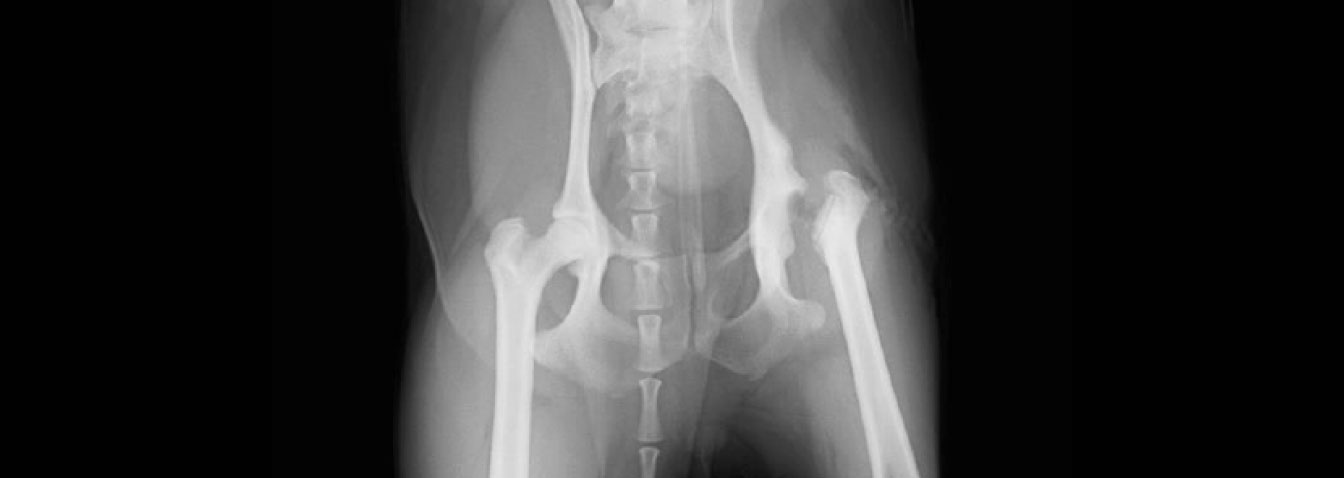

大腿骨頭切除(FHO)術後